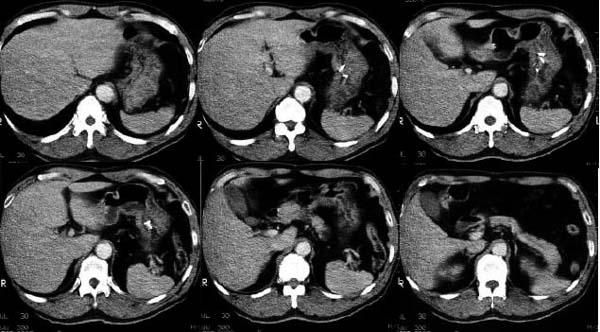

- Age/Sex:51M

- Chief Complaint:

- Clinical course:

2000擭4寧丄憗婜堓娻偺恌抐偱堓晹暘愗彍弍乮T1N0M0丄stage厽A丄

崻帯搙A乯傪庴偗偨丅弍拞銪懝彎偵傛傝銪揈傪庴偗偨丅偦偺屻奜棃偱宱夁娤嶡傪庴偗偰偄偨丅

- Images:

偁側偨偺恌抐偼 What

is your first impression?

What

is your first impression?

top